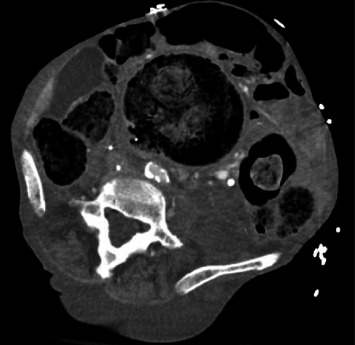

瘘管形成是解剖部位之间的连接,本质上是异常的。各种病因和相关结构存在这些异常发展。血管和肠系统之间的瘘管是罕见的。当存在时,解剖上的接近是决定涉及哪些结构的主要因素。主动脉肠瘘累及食道、十二指肠和小肠是众所周知的,胃也在罕见的情况下累及。瘘累及下腔静脉(IVC)和肠系统,也见过胃、小肠和胸内结肠介入手术后的瘘。我们报告了一位82岁的女性,她患有多种合并症,包括阿片类药物依赖、慢性便秘、下肢深静脉血栓形成、上消化道出血和下腔静脉滤器依赖,她出现了一个独特的问题。她的主诉是非特异性的,但最终诊断为下颌骨和乙状结肠之间的瘘管形成。本文所述的结肠瘘是文献中报道的第一例腹腔内瘘。

Fistula formation is a connection between anatomic locations that is intrinsically abnormal. A variety of causative etiologies and involved structures exist for these anomalous developments. Fistulas between vasculature and the enteric system are rare. When present, anatomical proximity is the dominant factor in determining which structures are involved. Aortoenteric fistulas involving the esophagus, duodenum, and small bowel are well-known with the stomach also being involved in rare instances. Fistulas involving the inferior vena cava (IVC) and enteric system have also been seen with the stomach, small bowel, and intrathoracic colon following an interposition each represented in reported cases. We present a case of an 82-year-old female with multiple medical comorbidities including opioid dependence, chronic constipation, recurrent lower extremity deep venous thrombosis, recurrent upper gastrointestinal (GI) bleeding, and IVC filter dependence who developed a unique problem. Her presenting complaints were nonspecific, but ultimately a diagnosis of fistula formation between the IVC and sigmoid colon was made. The colocaval fistula described here is the first intraperitoneal case to be reported in the body of literature.